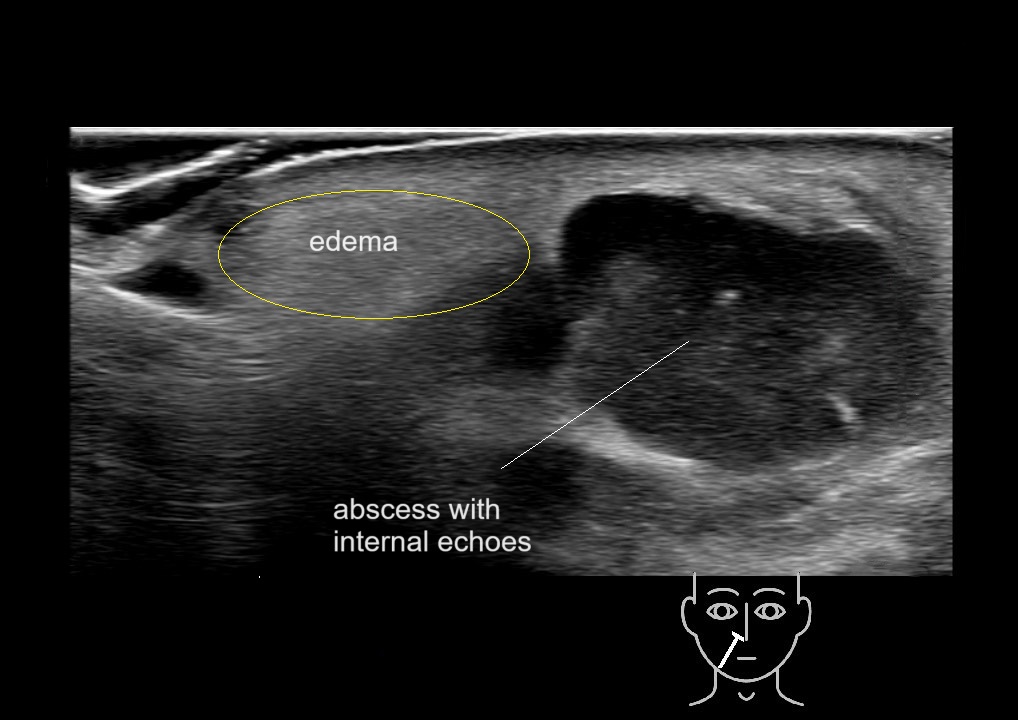

With ultrasound signs of inflammation can be visualized. Edema can be seen as a hyperechoic appearance of the subcutaneous fat, sometimes separated by hypoechoic fluid filled area’s, known as cobblestone appearance. Increased vascularization (hypervascularity) can be seen on colour Doppler. An abscess will appear as a fluid collection appearing as an irregular hypoechoic area with heterogeneous internal echoes and a thickened wall. Posterior acoustic enhancement can be present, and there is vascularity around but not within the mass. Under ultrasound guidance, abscesses can be managed by needle aspirations (18G) under antibiotic cover.

Study the first image to recognize the different layers. If you are sure about the layers, swipe to the second image to view the answer (if applicable).